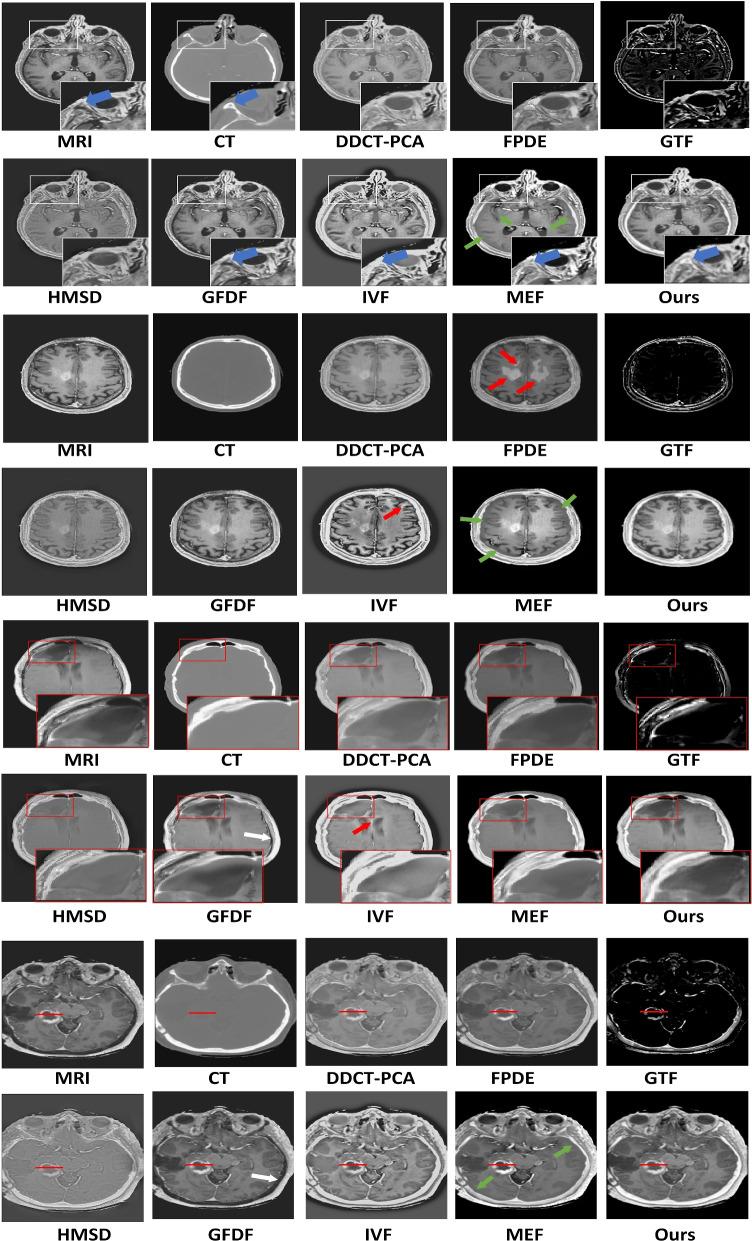

The MedFusionGAN successfully generates fused images with MRI soft-tissue and CT bone contrast. The results of the MedFusionGAN were quantitatively and qualitatively compared with seven traditional and eight deep learning (DL) state-of-the-art methods. Qualitatively, our method fused the source images with the highest spatial resolution without adding the image artifacts. We reported nine quantitative metrics to quantify the preservation of structural similarity, contrast, distortion level, and image edges in fused images. Our method outperformed both traditional and DL methods on six out of nine metrics. And it got the second performance rank for three and two quantitative metrics when compared with traditional and DL methods, respectively. To compare soft-tissue contrast, intensity profile along tumor and tumor contours of the fusion methods were evaluated. MedFusionGAN provides a more consistent, better intensity profile, and a better segmentation performance.

MedFusionGAN 成功地生成了具有 MRI 软组织和 CT 骨骼对比度的融合图像。MedFusionGAN 的结果与七种传统方法和八种深度学习(DL)最先进方法进行了定量和定性比较。定性方面,我们的方法以最高的空间分辨率融合了源图像,而没有添加图像伪影。我们报告了九个定量指标来量化融合图像中结构相似性、对比度、失真水平和图像边缘的保留情况。在九个指标中的六个指标上,我们的方法优于传统方法和 DL 方法。与传统方法和 DL 方法相比,在三个和两个定量指标上,我们的方法分别获得了第二和第三的性能排名。为了比较软组织对比度,对融合方法的肿瘤和肿瘤轮廓的强度曲线进行了评估。MedFusionGAN 提供了更一致、更好的强度曲线和更好的分割性能。